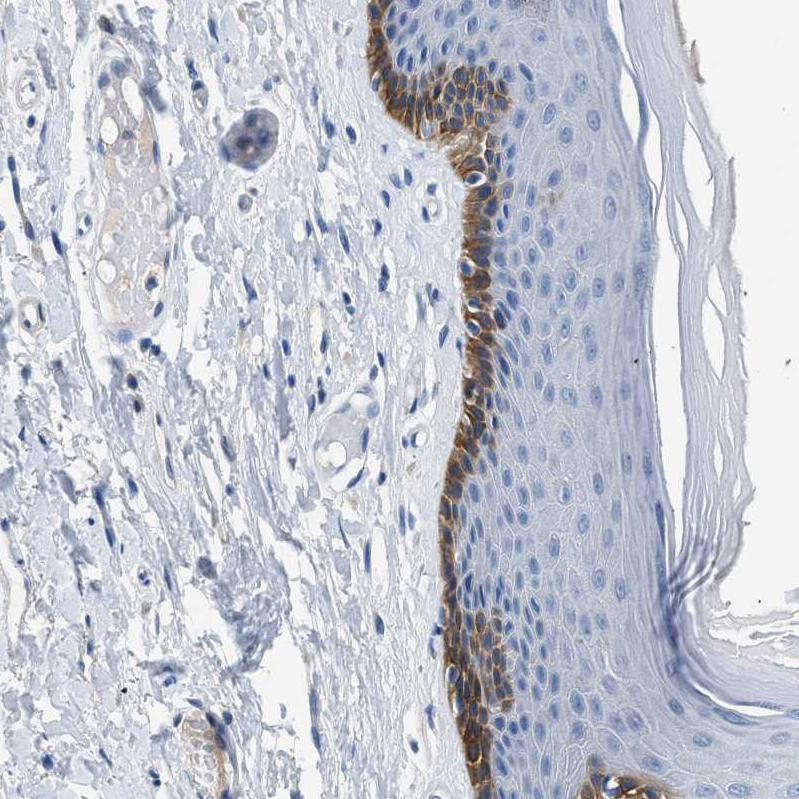

Immunohistochemistry analysis in human skin and lymph node tissues using HPA016662 antibody. Corresponding SLC10A6 RNA-seq data are presented for the same tissues.